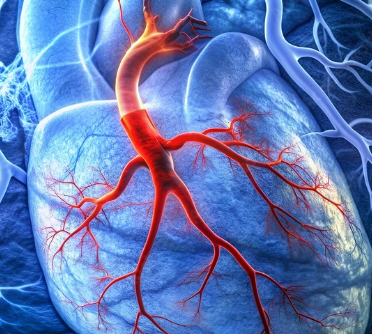

관상동맥 협착증은 심장을 둘러싸고 있는 관상동맥이 좁아져서 혈액 공급이 제대로 이루어지지 않는 상태를 말합니다. 이는 심장에 산소와 영양분을 전달하는 데 중요한 역할을 하므로, 조기에 진단하고 적절히 치료하는 것이 중요합니다. 이번 글에서는 관상동맥 협착증의 치료 방법에 대해 알아보고, 최신 연구와 치료 트렌드를 포함하여 자세히 설명하겠습니다.

관상동맥 협착증은 혈관 내벽에 플라크(지방, 콜레스테롤 등)가 축적되면서 혈관이 좁아지는 질환입니다. 이로 인해 심장으로 가는 혈류량이 줄어들게 되며, 심각할 경우 협심증이나 심근경색과 같은 치명적인 합병증으로 이어질 수 있습니다.